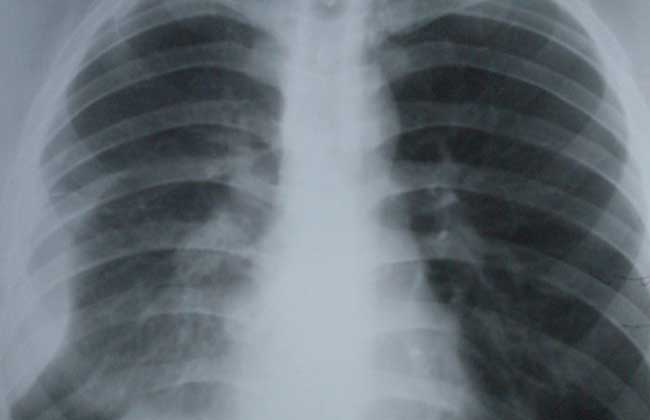

胸膜炎是指由致病因素(通常为病毒或细菌)刺激胸膜所致的胸膜炎症,胸腔内可伴液体积聚(渗出性胸膜炎)或无液体积聚(干性胸膜炎),炎症控制后胸膜可恢复至正常,或发生两层胸膜相互粘连,临床主要表现为胸痛、咳嗽、胸闷、气急,甚则呼吸困难,下面我们就一起来看一看胸膜炎是怎么引起的吧!

胸痛是胸膜炎最常见的症状,常突然发生,程度差异较大,可为不明确的不适或严重的刺痛或仅在患者深呼吸或咳嗽时出现,也可持续存在并因深呼吸或咳嗽而加剧。胸痛是由壁层胸膜的炎症引起,出现于正对炎症部位的胸壁,也可表现为腹部、颈部或肩部的牵涉痛。深呼吸可致疼痛,引起呼吸浅快,患侧肌肉运动较对侧为弱。若发生大量积聚,可致两层胸膜相互分离,则胸痛可消失。大量胸腔积液可致呼吸时单侧或双侧肺活动受限,发生呼吸困难。